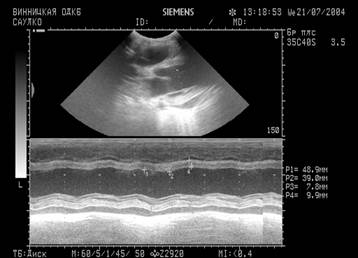

Дівчинка 11 міс. Cкарги батьків на швидку її втомлюваність при годуванні, раптове посилення ціанозу та задухи при плачі. Об¢єктивно: Стан середньої важкості, відставання в фізичному розвитку. В спокої – помірно виражений ціаноз шкірних покривів, слизові з фіолетовим відтінком, ціаноз посилюється при плачі дитини. Під час огляду на фоні неспокою значно посилився ціаноз, почастішало дихання, дитина стала вкрай неспокійною, на руках у матері з притиснутими до живота ніжками трохи заспокоїлась. Дихання 64 на хв, над легенями ясний перкуторний звук, жорстке дихання Пульс 150 за хв. Межі серця: розширені вправо. Над всією поверхнею грудної клітки вислуховується грубий систолічний шум із максимальною звучністю в 2-му міжребер'ї зліва від грудини, другий тон ослаблений над легеневою артерією. Загальний аналіз крові: Hb -200 г/л; еритроцити – 6,0 Т/л, КП – 0,95; нейтрофіли: паличкоядерні -5%, сегментоядерні -39%; еозинофіли-3%; лімфоцити-50%; моноцити - 3%; ШЗЕ - 4 мм/год. Рентгенологічне обстеження ОГК: див. рис.

Дівчинка 11 міс. Cкарги батьків на швидку її втомлюваність при годуванні, раптове посилення ціанозу та задухи при плачі. Об¢єктивно: Стан середньої важкості, відставання в фізичному розвитку. В спокої – помірно виражений ціаноз шкірних покривів, слизові з фіолетовим відтінком, ціаноз посилюється при плачі дитини. Під час огляду на фоні неспокою значно посилився ціаноз, почастішало дихання, дитина стала вкрай неспокійною, на руках у матері з притиснутими до живота ніжками трохи заспокоїлась. Дихання 64 на хв, над легенями ясний перкуторний звук, жорстке дихання Пульс 150 за хв. Межі серця: розширені вправо. Над всією поверхнею грудної клітки вислуховується грубий систолічний шум із максимальною звучністю в 2-му міжребер'ї зліва від грудини, другий тон ослаблений над легеневою артерією. Загальний аналіз крові: Hb -200 г/л; еритроцити – 6,0 Т/л, КП – 0,95; нейтрофіли: паличкоядерні -5%, сегментоядерні -39%; еозинофіли-3%; лімфоцити-50%; моноцити - 3%; ШЗЕ - 4 мм/год. Рентгенологічне обстеження ОГК: див. рис.

1. Який попередній діагноз? Яке ускладнення розвинулось у дитини? Опишіть патологічні зміни в аналізі крові, на ЕКГ, ЕхоКГ та на рентгенограмі.